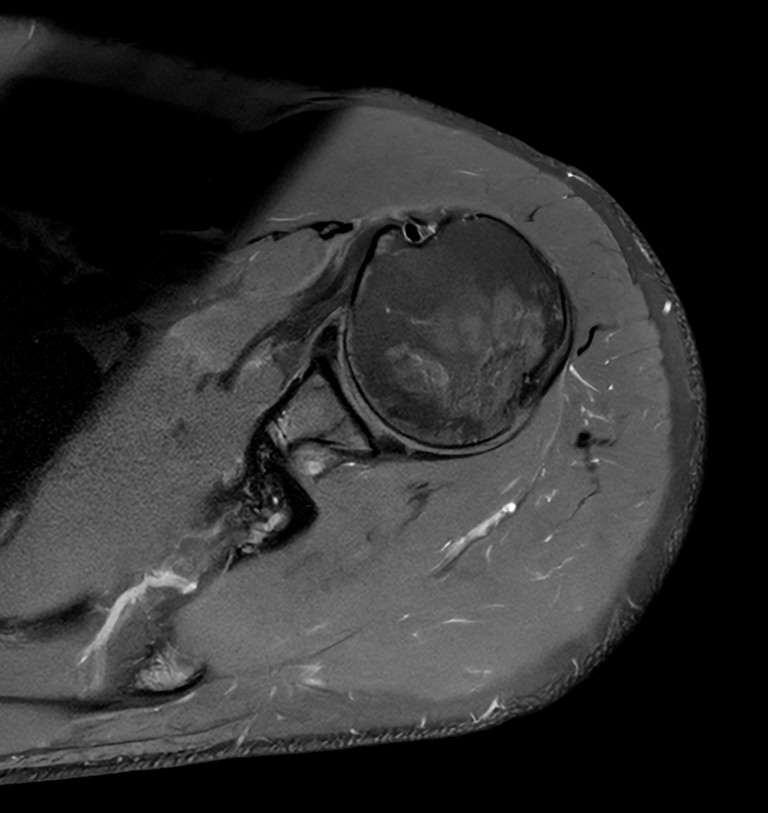

High quality Shoulder imaging with SmartSpeed Precise